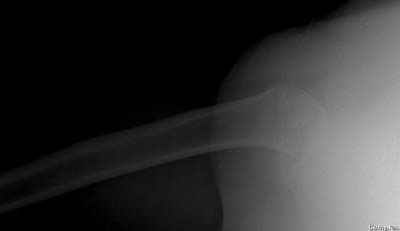

Посылаю послеоперационные Рг граммы.

Всего Доброго,

Поздравляю, получилось просто замечательно. Если можно, расскажи чуть подробнее, как делали - как вправляли, как вводили спицы, поворачивали ли их?

Спасибо за поздравления:-))

Я и сам доволен результатом. В предпоследнем письме я кратко описал ход операции - закрыто репонировать не удалось( 2 недели с момента травмы и 1 неделя после неудачной репозиции) после удаления пучков спиц, пришлось сделать - 2см разрез на уровне перелома и с помощью периостального элеватора (золотое правило механики) *одеть* головку на дистальный отломок.

Спицы проводил через старые отверстия, вращая пучок импактором- направителем при его введении в головку.